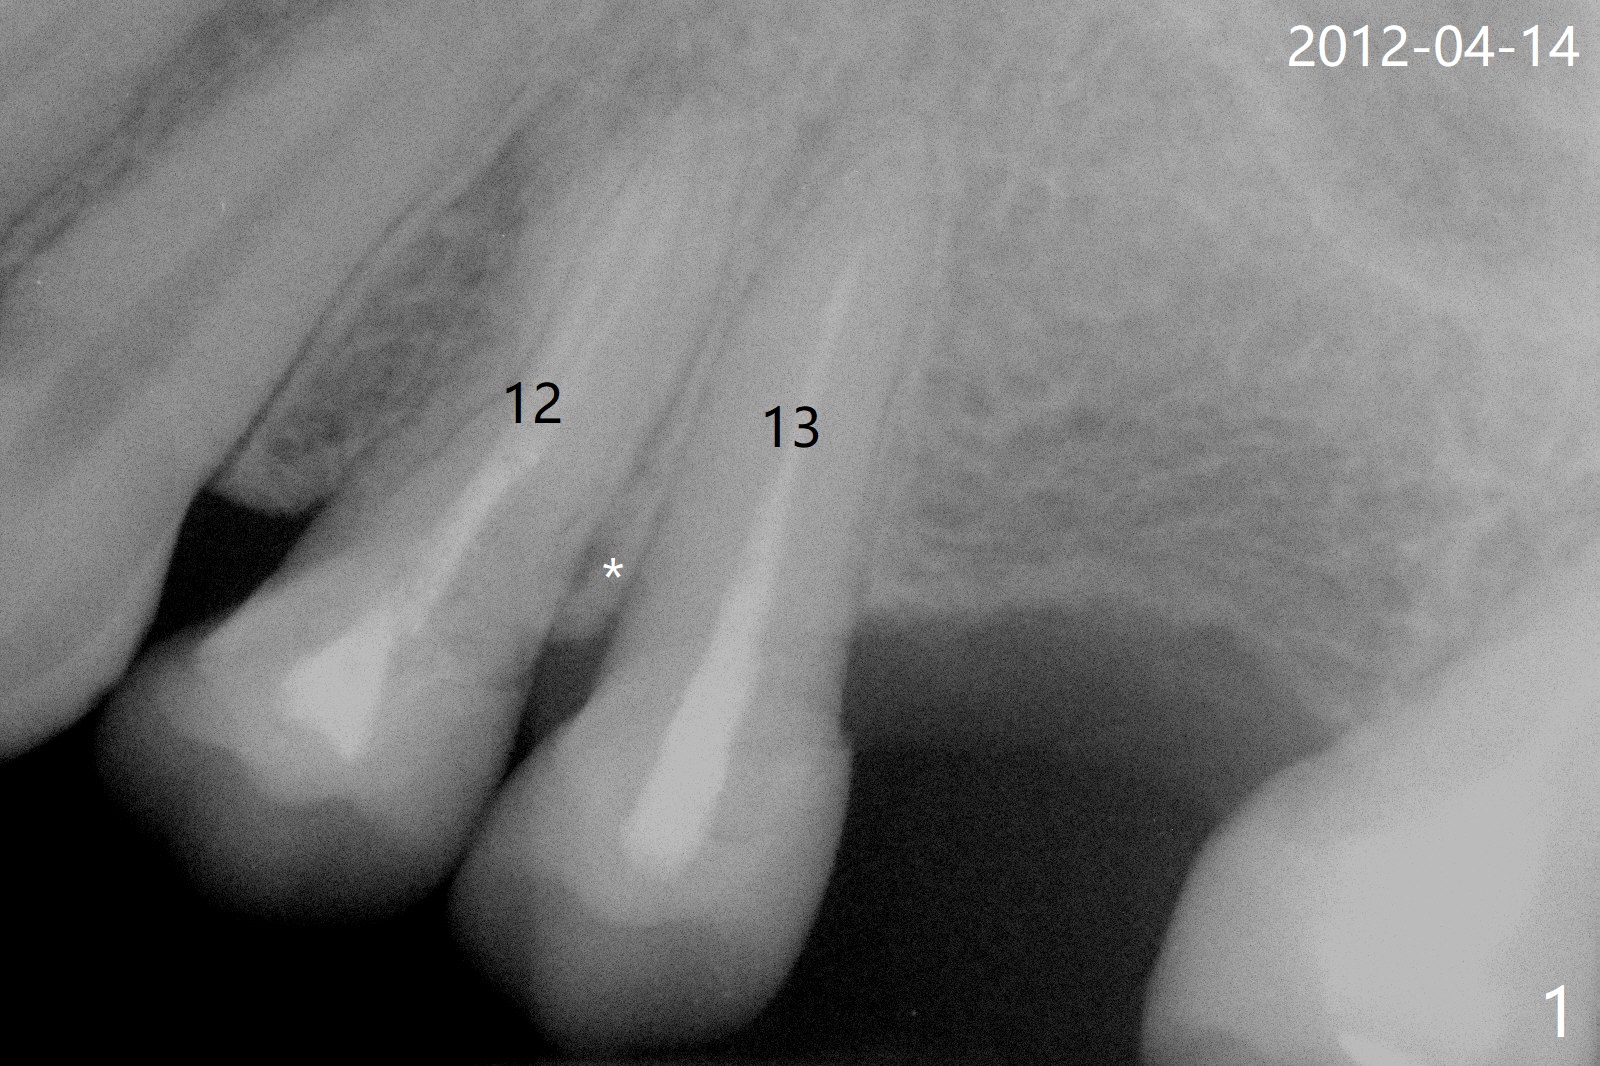

42岁女,12号牙断裂(图一),在拔除中不幸损伤13号牙,一起拔除,用GEM21S与异体骨和人工骨进行位点保存,术后骨粉一直脱落,病人觉得伤口有臭味。术后16天根尖片显示骨粉仍在牙槽窝(图二),伤口尚未愈合(图三),骨粉密度不高(图四,五)。讨论后,决定去除余留骨粉,重新刮拔牙槽窝,反复冲洗,最好放置粘性骨粉(图六),覆盖PRF和不可吸收膜,使用PTFE缝线,树脂敷料。术后三周膜和骨粉仍在原位(图七,八)。为了恢复龈乳头,术后四,五个月,利用导板去除两个牙位牙槽嵴骨质(图九),把植体植入牙槽嵴深部,之间便形成突起的牙槽嵴(图十:C)以及龈乳头。植牙整合后,利用临时牙冠,反复调整,挤压形成比较正常龈乳头。